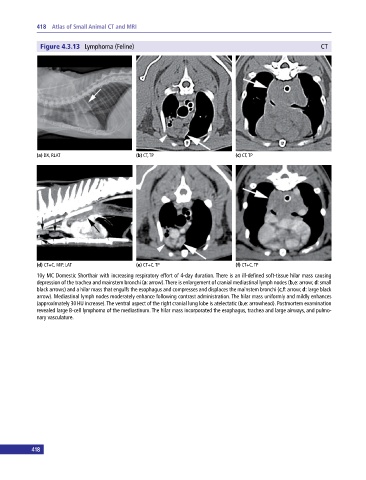

Figure 4.3.13 Lymphoma (Feline) CT

(a) DX, RLAT (b) CT, TP (c) CT, TP

(d) CT+C, MIP, LAT (e) CT+C, TP (f) CT+C, TP

10y MC Domestic Shorthair with increasing respiratory effort of 4‐day duration. There is an ill‐defined soft‐tissue hilar mass causing

depression of the trachea and mainstem bronchi (a: arrow). There is enlargement of cranial mediastinal lymph nodes (b,e: arrow; d: small

black arrows) and a hilar mass that engulfs the esophagus and compresses and displaces the mainstem bronchi (c,f: arrow; d: large black

arrow). Mediastinal lymph nodes moderately enhance following contrast administration. The hilar mass uniformly and mildly enhances

(approximately 30 HU increase). The ventral aspect of the right cranial lung lobe is atelectatic (b,e: arrowhead). Postmortem examination

revealed large B‐cell lymphoma of the mediastinum. The hilar mass incorporated the esophagus, trachea and large airways, and pulmo

nary vasculature.